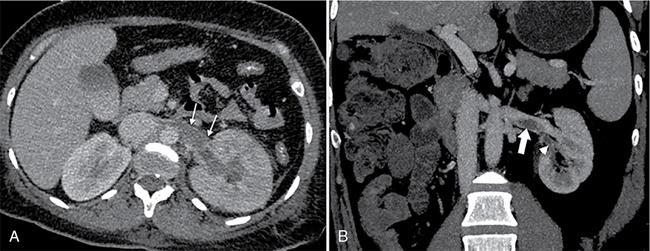

• Heterogeneously enhancing filling defect in renal vein with luminal expansion and having continuity with the renal mass (Fig. 10.18.1.9).

Fig. 10.18.1.9 (A) Axial and (B) coronal CT images of right kidney showing heterogeneously enhancing mass lesion infiltrating renal vein (arrows) and extending into the IVC, suggesting tumour thrombosis. Also note nonenhancing thrombus in the IVC (arrowhead).